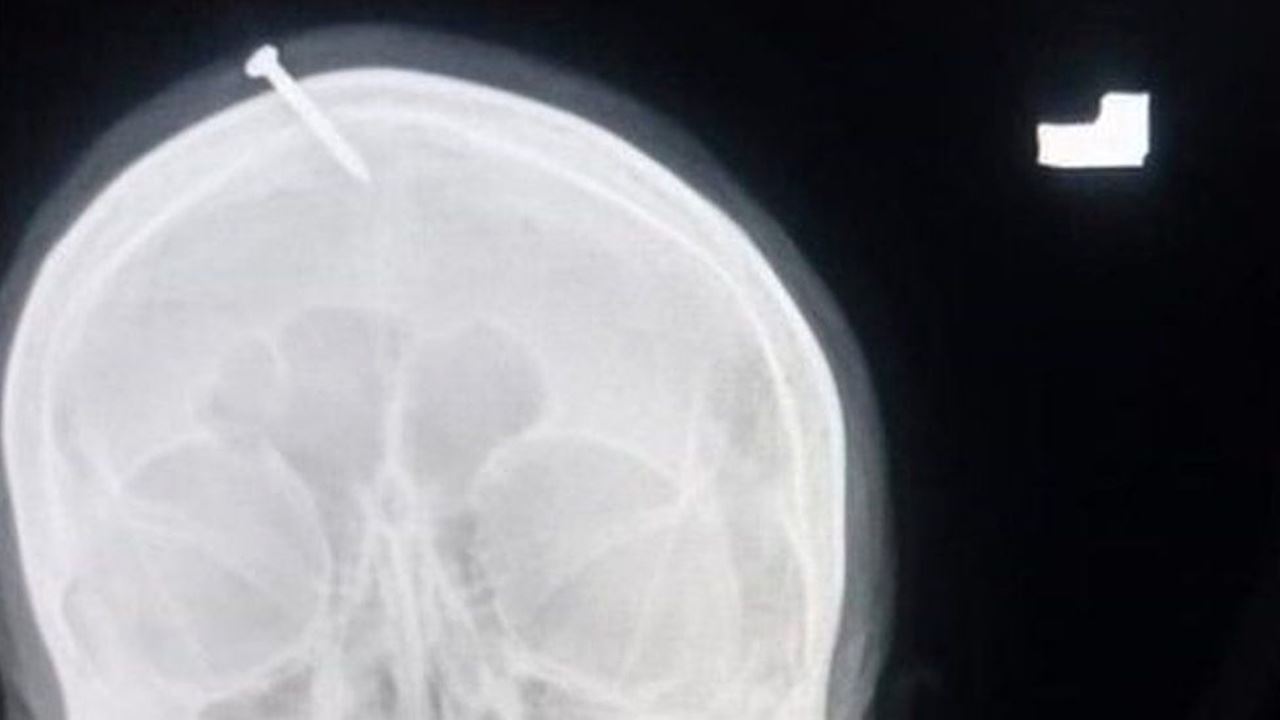

Imbasan X-ray menunjukkan paku itu terbenam dalam tengkorak kepalanya, namun mujur ia tidak mengenai bahagian otak.

“Kita dapati tukul atau objek berat digunakan bagi memasukkan paku ke dalam kepalanya.

“Dia masih sedar sepenuhnya tetapi dalam keadaan terlalu sakit,” katanya.